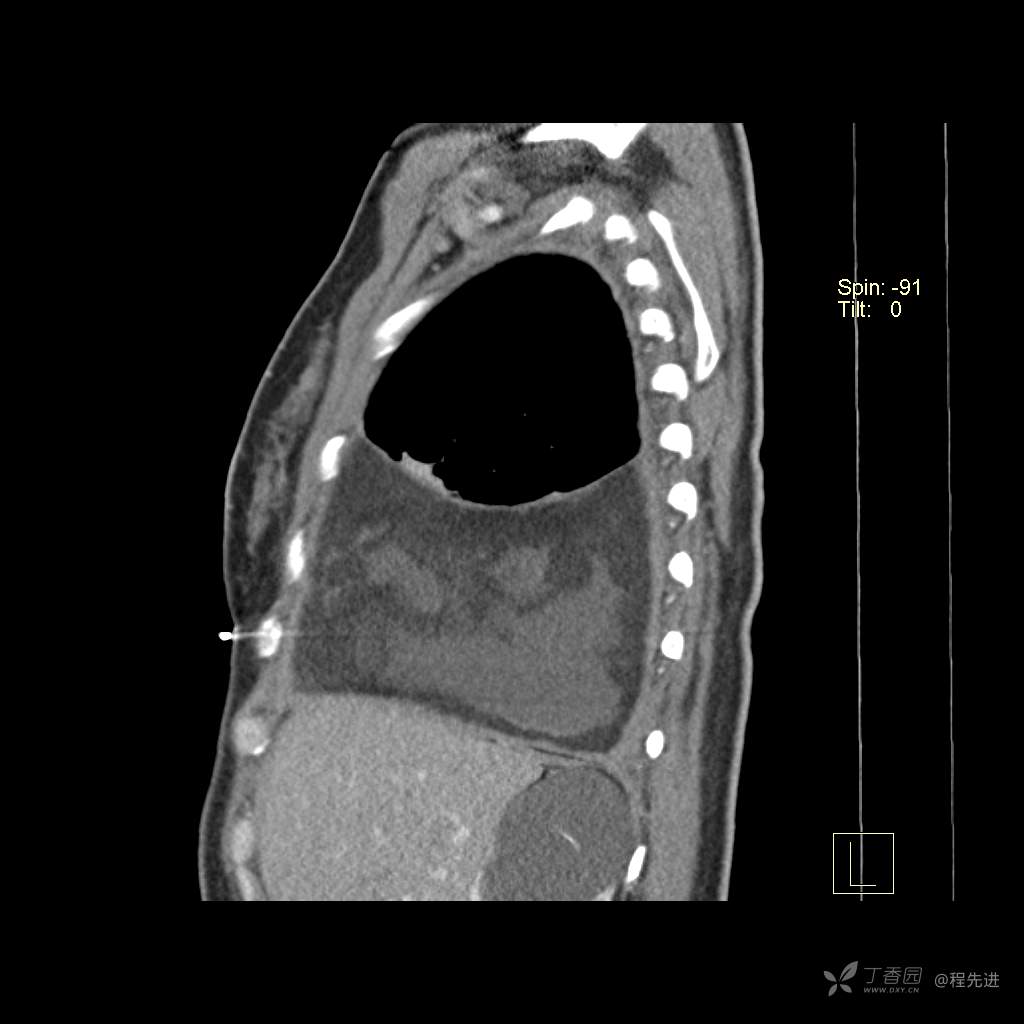

患者性别:女

患者年龄:51岁

简要病史:胸闷半年

肺淋巴管肌瘤病 (7)

乳糜胸 (8)